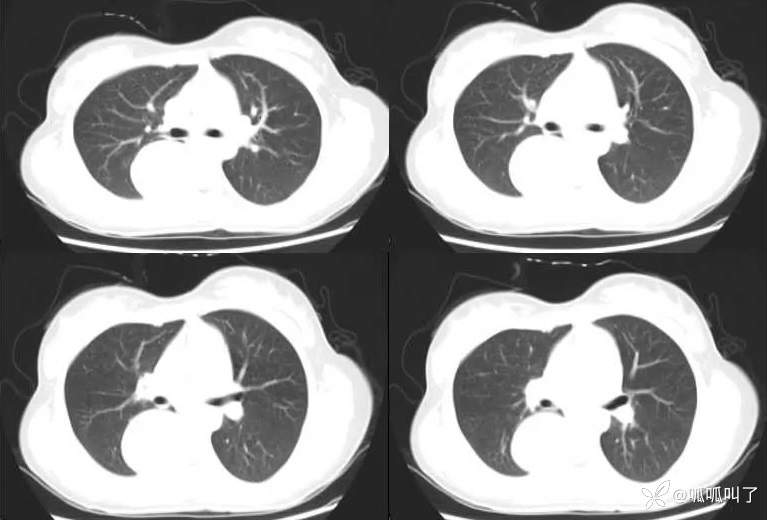

病史:女,17岁,高中学生,学校体检发现纵隔肿物,平素无明显不适症状,建议进一步检查,次日就诊于当地医院行胸部CT提示“右肺下叶脊柱旁占位”,建议入院治疗,后就诊于我院。

既往史:曾患先天性白内障并手术治疗。

CT